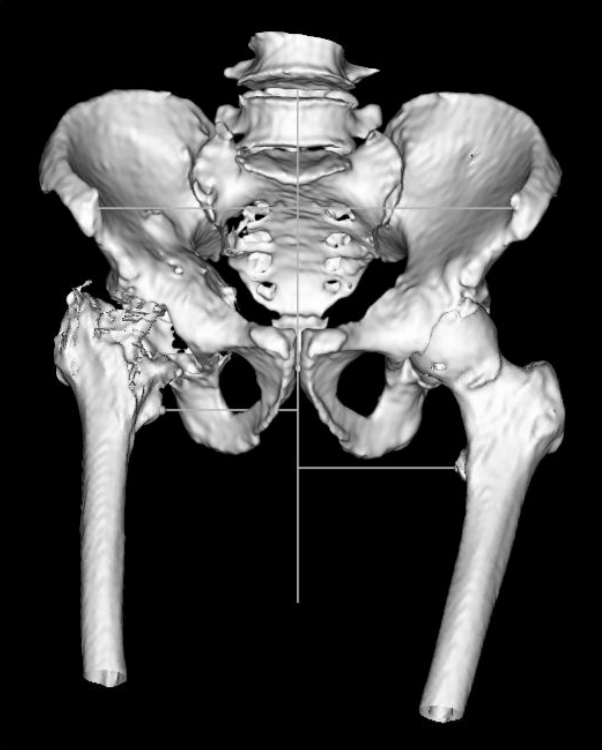

近日,由浙江大学医学院附属第一医院雷鹏飞教授团队顺利完成浙江首台VTS可视化智能辅助系统配合爱康HDR翻修系统+个性化定制3D打印多孔金属补块的复杂翻修手术。术中使用72毫米直径髋臼杯,结合3D打印个性化定制翻修补块,在VTS系统辅助下精准放置于规划位置,成功修复髋臼巨大骨缺损。

术后雷鹏飞教授表示,VTS系统与HDR系统首次搭档获得了良好的术后效果,VTS系统的引入让复杂手术简单化,术前规划让手术更安全,术中辅助指引让手术更精准。HDR定制外杯采用非组配设计,假体整体为EBM技术3D打印多孔结构,具有较高的粗糙度和摩擦系数。由于无需设计与内衬的连接结构,因此螺钉孔的布置更加灵活,为俗称的“满天星”设计,便于在残留的宿主骨上进行螺钉固定,实现牢靠的初始稳定性。